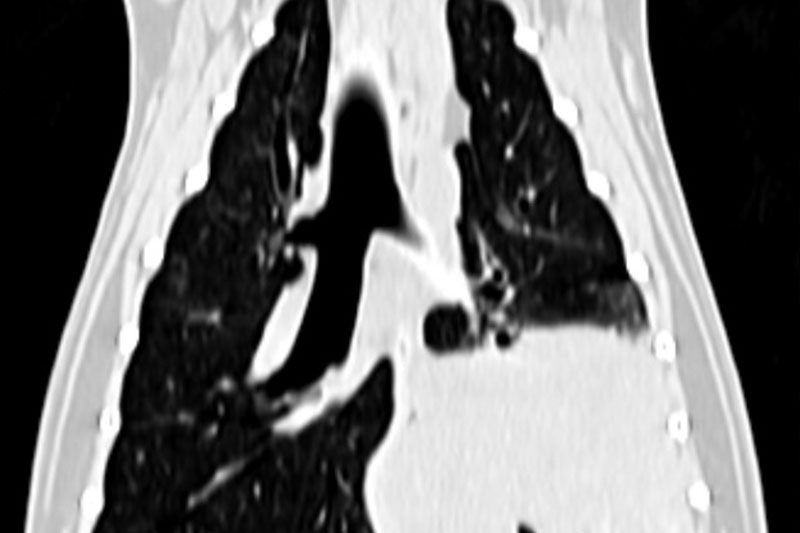

CT (Computed Tomography, 전산화 단층촬영) 검사는 X-ray를 이용해 반려동물의 몸을 여러 각도에서 촬영하고, 이를 컴퓨터로 합성하여 단면 이미지(슬라이스)를 만들어내는 정밀 진단 장비입니다.

사람 병원에서도 널리 사용하는 기술로, 뼈, 장기, 혈관, 종양 등 몸속 구조를 3차원(3D)으로 시각화할 수 있습니다.

| 흉부(가슴) | 폐종양, 늑골 골절, 기관지 협착, 심장 주변 병변 등 |

폐 질환의 상세 평가